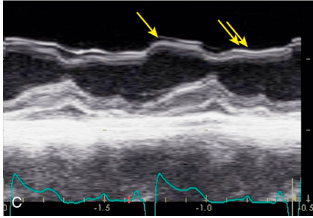

Pericardial “rind” or thickening of the visceral pericardium

Secondary to inflammation related to acute pericarditis.

Best seen adjacent to the lateral wall of the left ventricle.

What are the arrows pointing to?